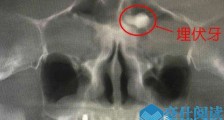

- 额头竟长了一颗牙怎么回事 额头藏牙原因揭秘真相令人惊【热点】

- 要是有人跟你说,额头上长有牙,你信吗?近日,在深圳某医院里,一名中年男子的额头,竟然长了一颗牙!在经过CBCT拍摄发现,该名男子额头“藏”有牙,这还真是闻所未闻的世间“奇事”啊!下面,就...